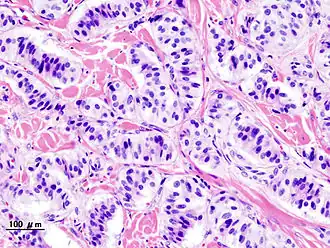

Histopatología de tumor del páncreas endocrino (insulinoma). | ||